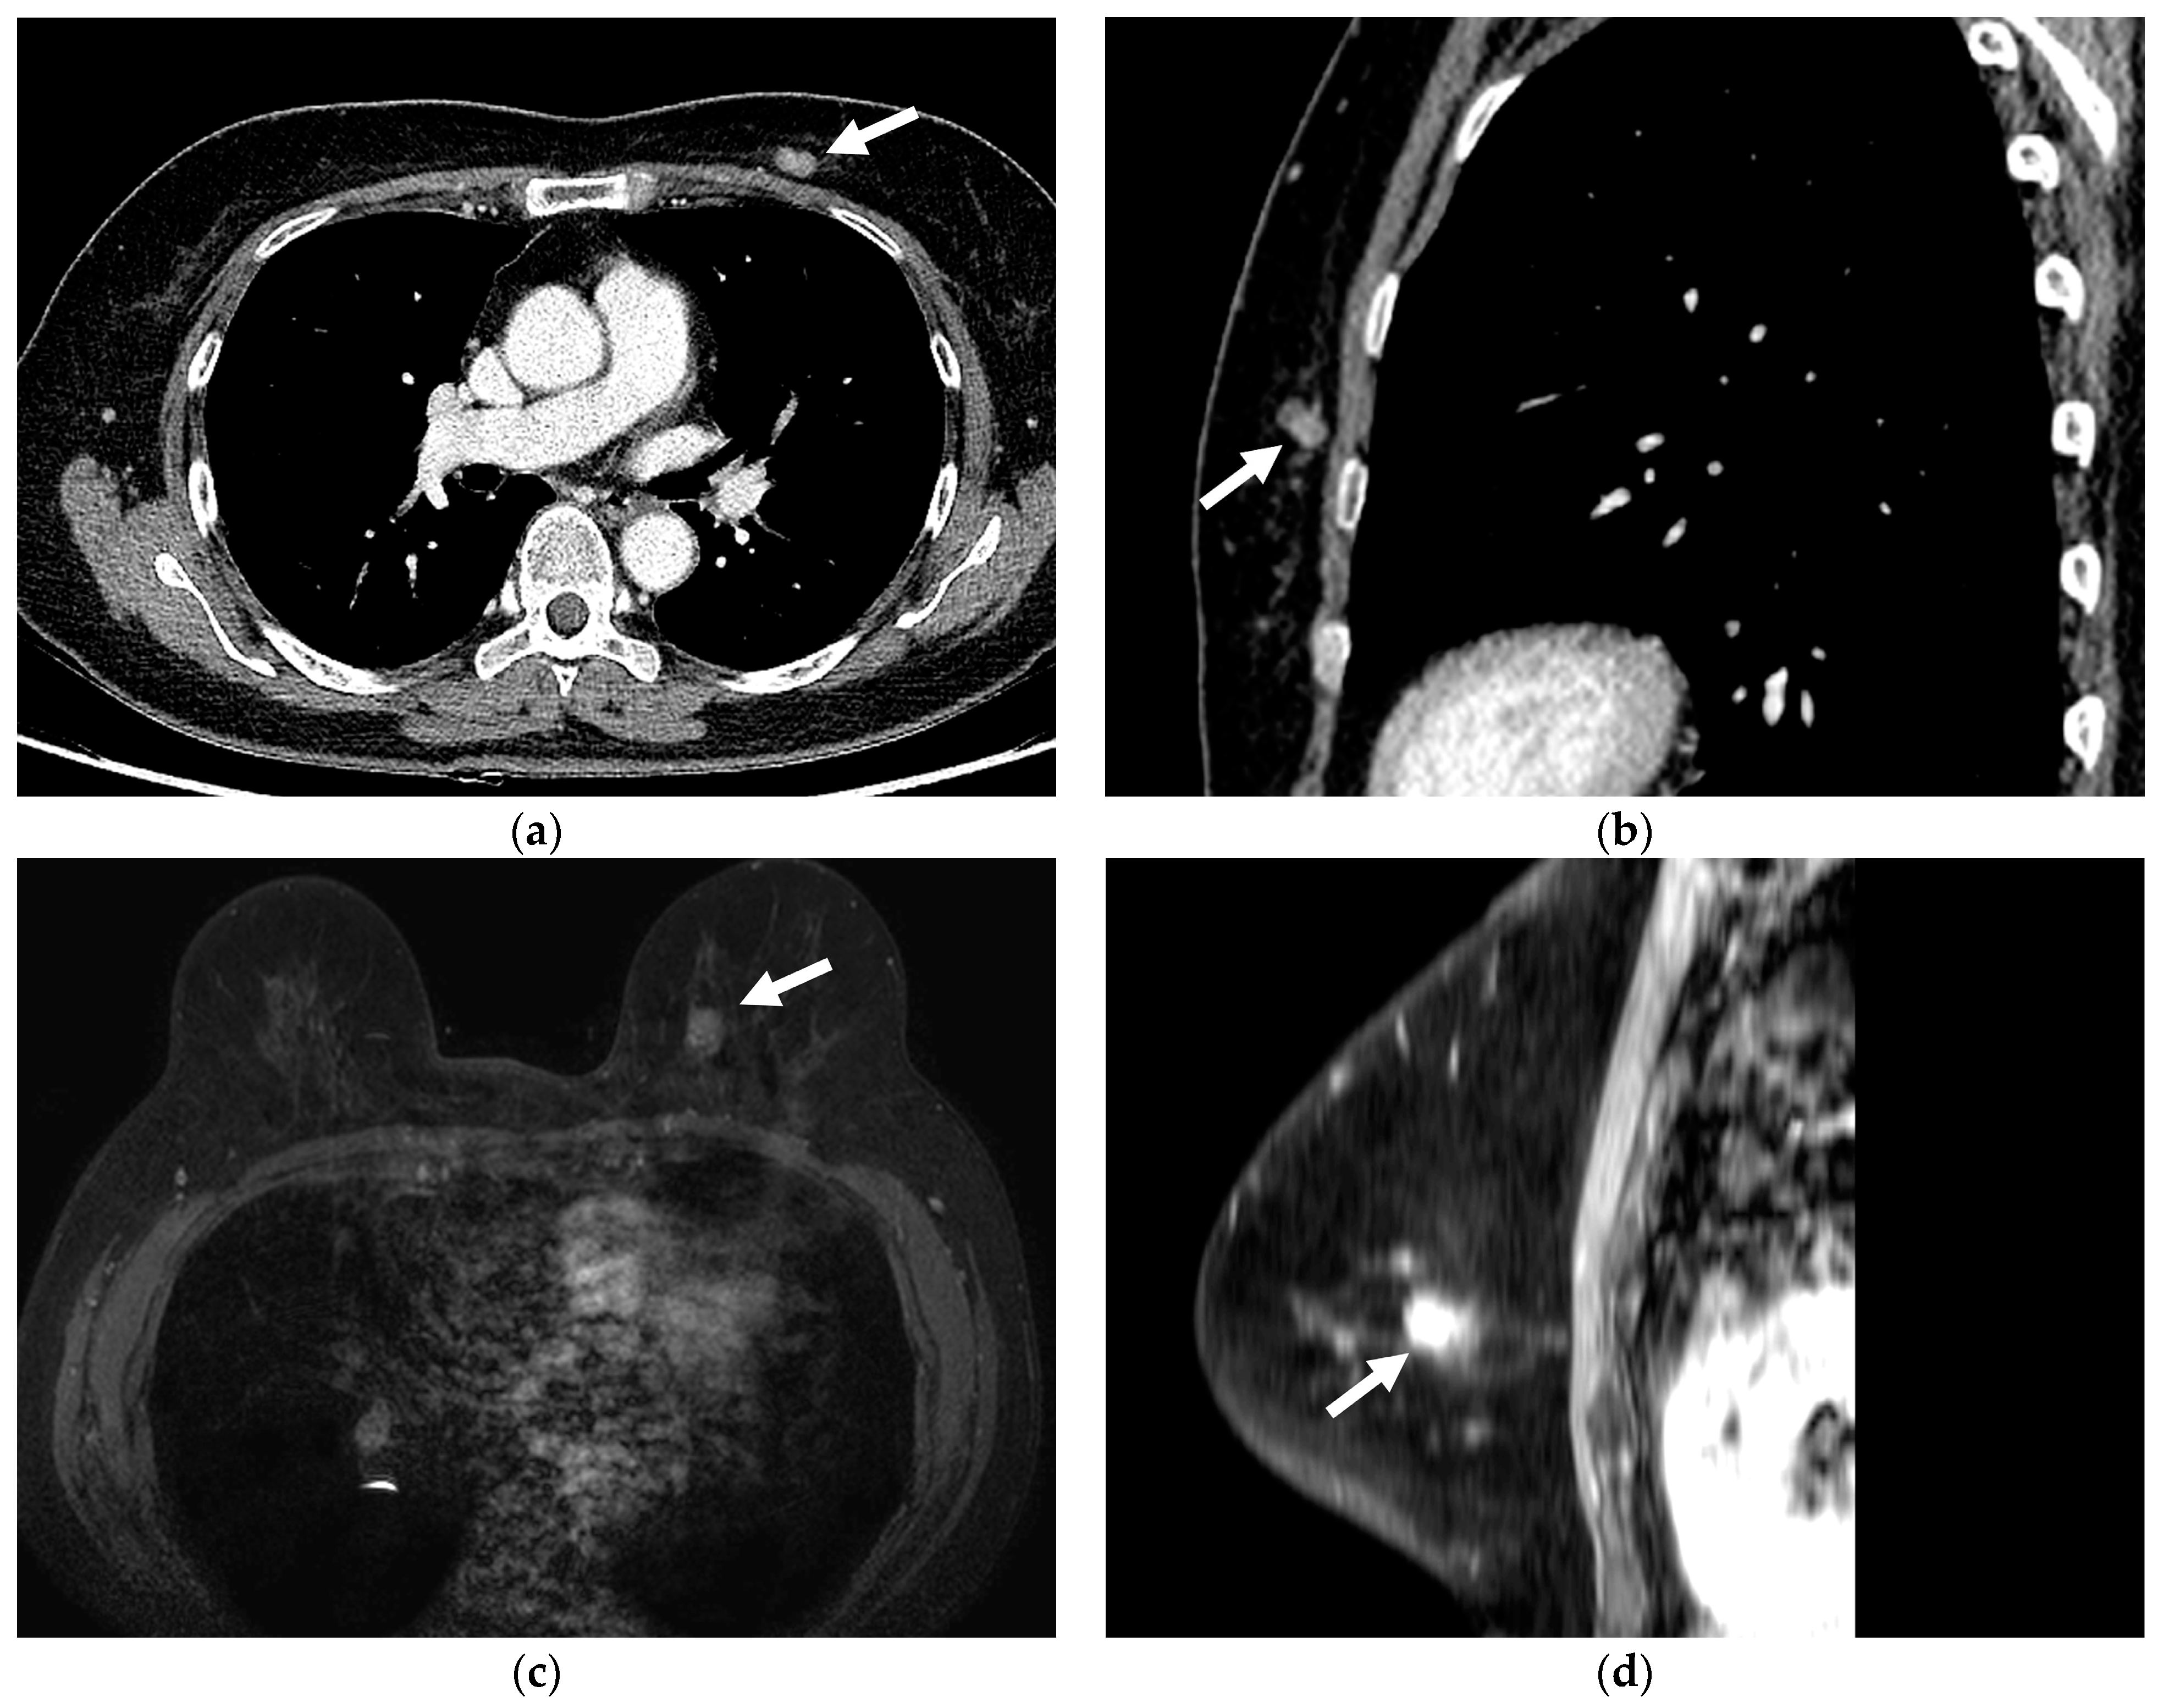

3.2. Imaging Features of Missed and Detected Breast Cancers

3.3. Imaging Features Associated with Missed Breast Lesions Group